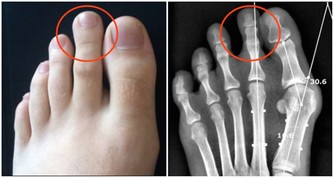

3、肝掌:

與常人的手掌顏色大不相同,普通人的手掌顏色紅潤,而患有肝病的病人手掌心泛白無血色。

6、肝掌蜘蛛痣:

很多慢性肝病會出現肝掌、蜘蛛痣、肝病面容,尤其肝硬化病人比較多見。

但是肝掌和蜘蛛痣沒有特異性,在正常人中同樣可以見到,因此不能人有蜘蛛痣或肝掌就說是肝病症狀。